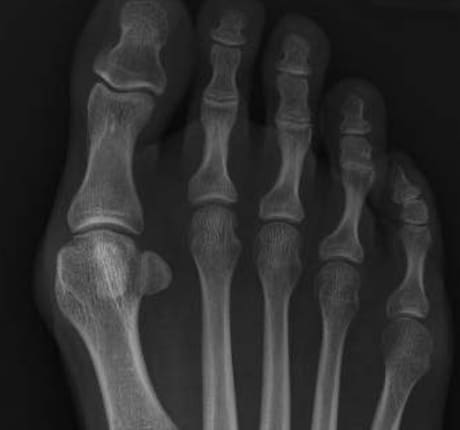

Röntgenbild präoperativ

Hallux valgus, rechts